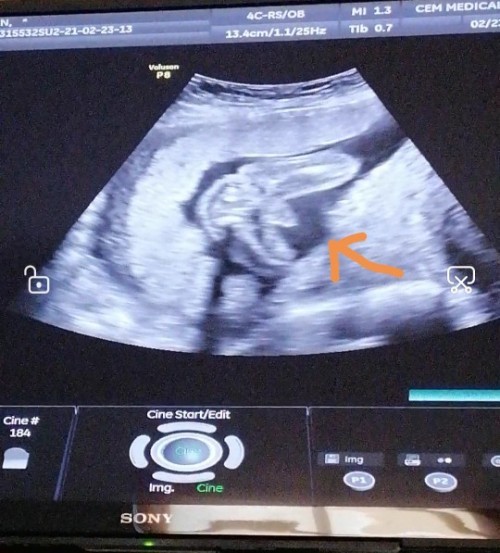

Hi mga momsh tanung ko lang db accurate naman na boy ang baby ko kahit 23 weeks plng ako CAS kahapon, may lawit, eh meron nagsasabi pag 5months hindi pa sure gender,? Db boy po yan. Salamat #FTM

yes po. akin po 18 weeks

Its a baby boy din po...

Post reply image